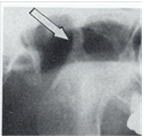

パノラマX線写真にて、顎関節の異常が44,3%に認められます。

下顎頭の平坦化(71.4%)、萎縮、消失が生じます。

関節リウマチの進行に伴い下顎頭のX線所見に異常が多く認められます。

1)下顎頭の破壊(X線所見の分類、三上、1992)

正常な顎関節

1;関節頭の平坦化

2;関節頭の萎縮

3;関節頭の消失

顎関節の下顎頭のX線変化は40〜80%位です。